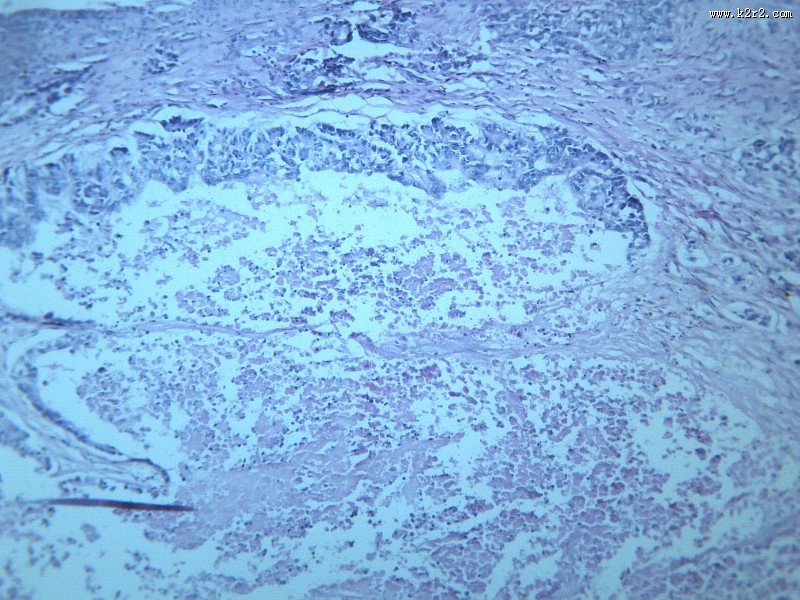

腺癌肝转移大全 - 第10张

腺癌肝转移大全

图集中 / 共有 12 张图片

淋巴结内转移癌

腺癌

医学

显微切片

癌症

腺癌肝转移